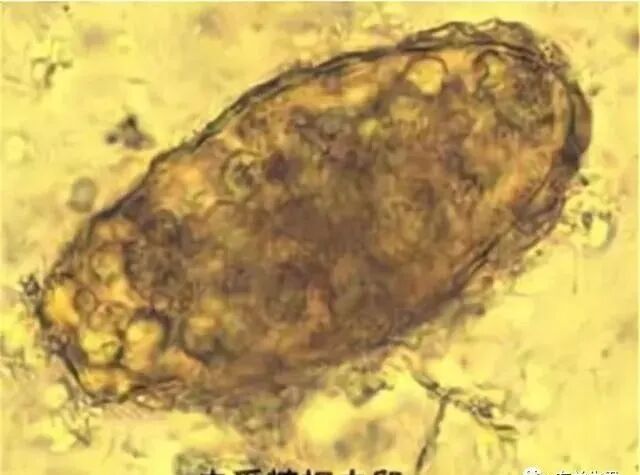

蛔虫属于线虫动物门,是人体内最常见的一种寄生虫,主要寄生在小肠中,最长能够长到35cm,它会像蚯蚓一样在人的肠道中蠕动,随着粪便被排出。

外形:

蛔虫的外形很像蚯蚓,但是没有蚯蚓那么明显的头,外表虽有横纹但是看起来很光滑,颜色白中带黄或者是淡粉色;雄性尾部微卷,个头直径比较大,雌性则通体直,个头比较小。

无法被肠胃消化:

蛔虫能在人的肠胃中寄生、不会被消化掉,主要是有一层保护膜——抗寄主消化酶的弹性角质膜。

这个角质膜耐腐蚀性强,能够抵挡任何物理、化学及各种生物性损伤,具有极强的纵向弹性,同时能够维持体内的液压保持一个饱满的形态,人体不存在能够将其分解的消化酶。